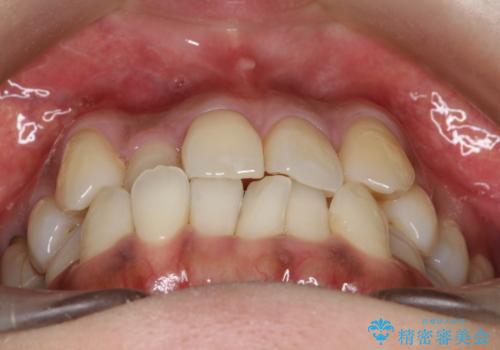

【審美装置】抜歯の本数最小限で行った矯正治療

- 治療計画

- 全体のがたつきを主訴に来院されました。4番目の歯を4本抜歯も検討しましたが、口元が下がりすぎてしまうリスクと2番目の転位うが著しく並べるのにかかる期間を考慮し、変則的な抜歯をし、並べる計画を立てました。

抜歯矯正のため2年はかかってしまいましたが、きれいに並び患者様にも満足頂きました。